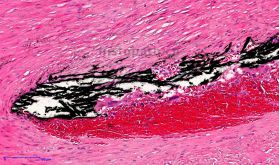

Von Kossa染色原理:

钙在人体内大量存在,构成骨骼作为支持人体的支架,在分泌、运送、肌肉收缩、神经传导等方面也起重要作用。许多染料可以与钙形成螯合物,包括茜素红S、红紫素、核固红等。茜素红S属一种蒽醌类衍生物,是茜素磺酸钠盐,它能与碳酸钙或磷酸钙中的钙盐螯合形成橙红色复合物。钙盐染色常用方法有Von Kossa溶液和茜素红S法,本产品原理在于该法是一种金属置换法,Von Kossa银溶液作用于含有不溶性钙盐的切片时,钙被银所置换,银盐在光的作用下被还原为黑色金属银,适用于大量样本的钙盐组织染色。

染色结果: